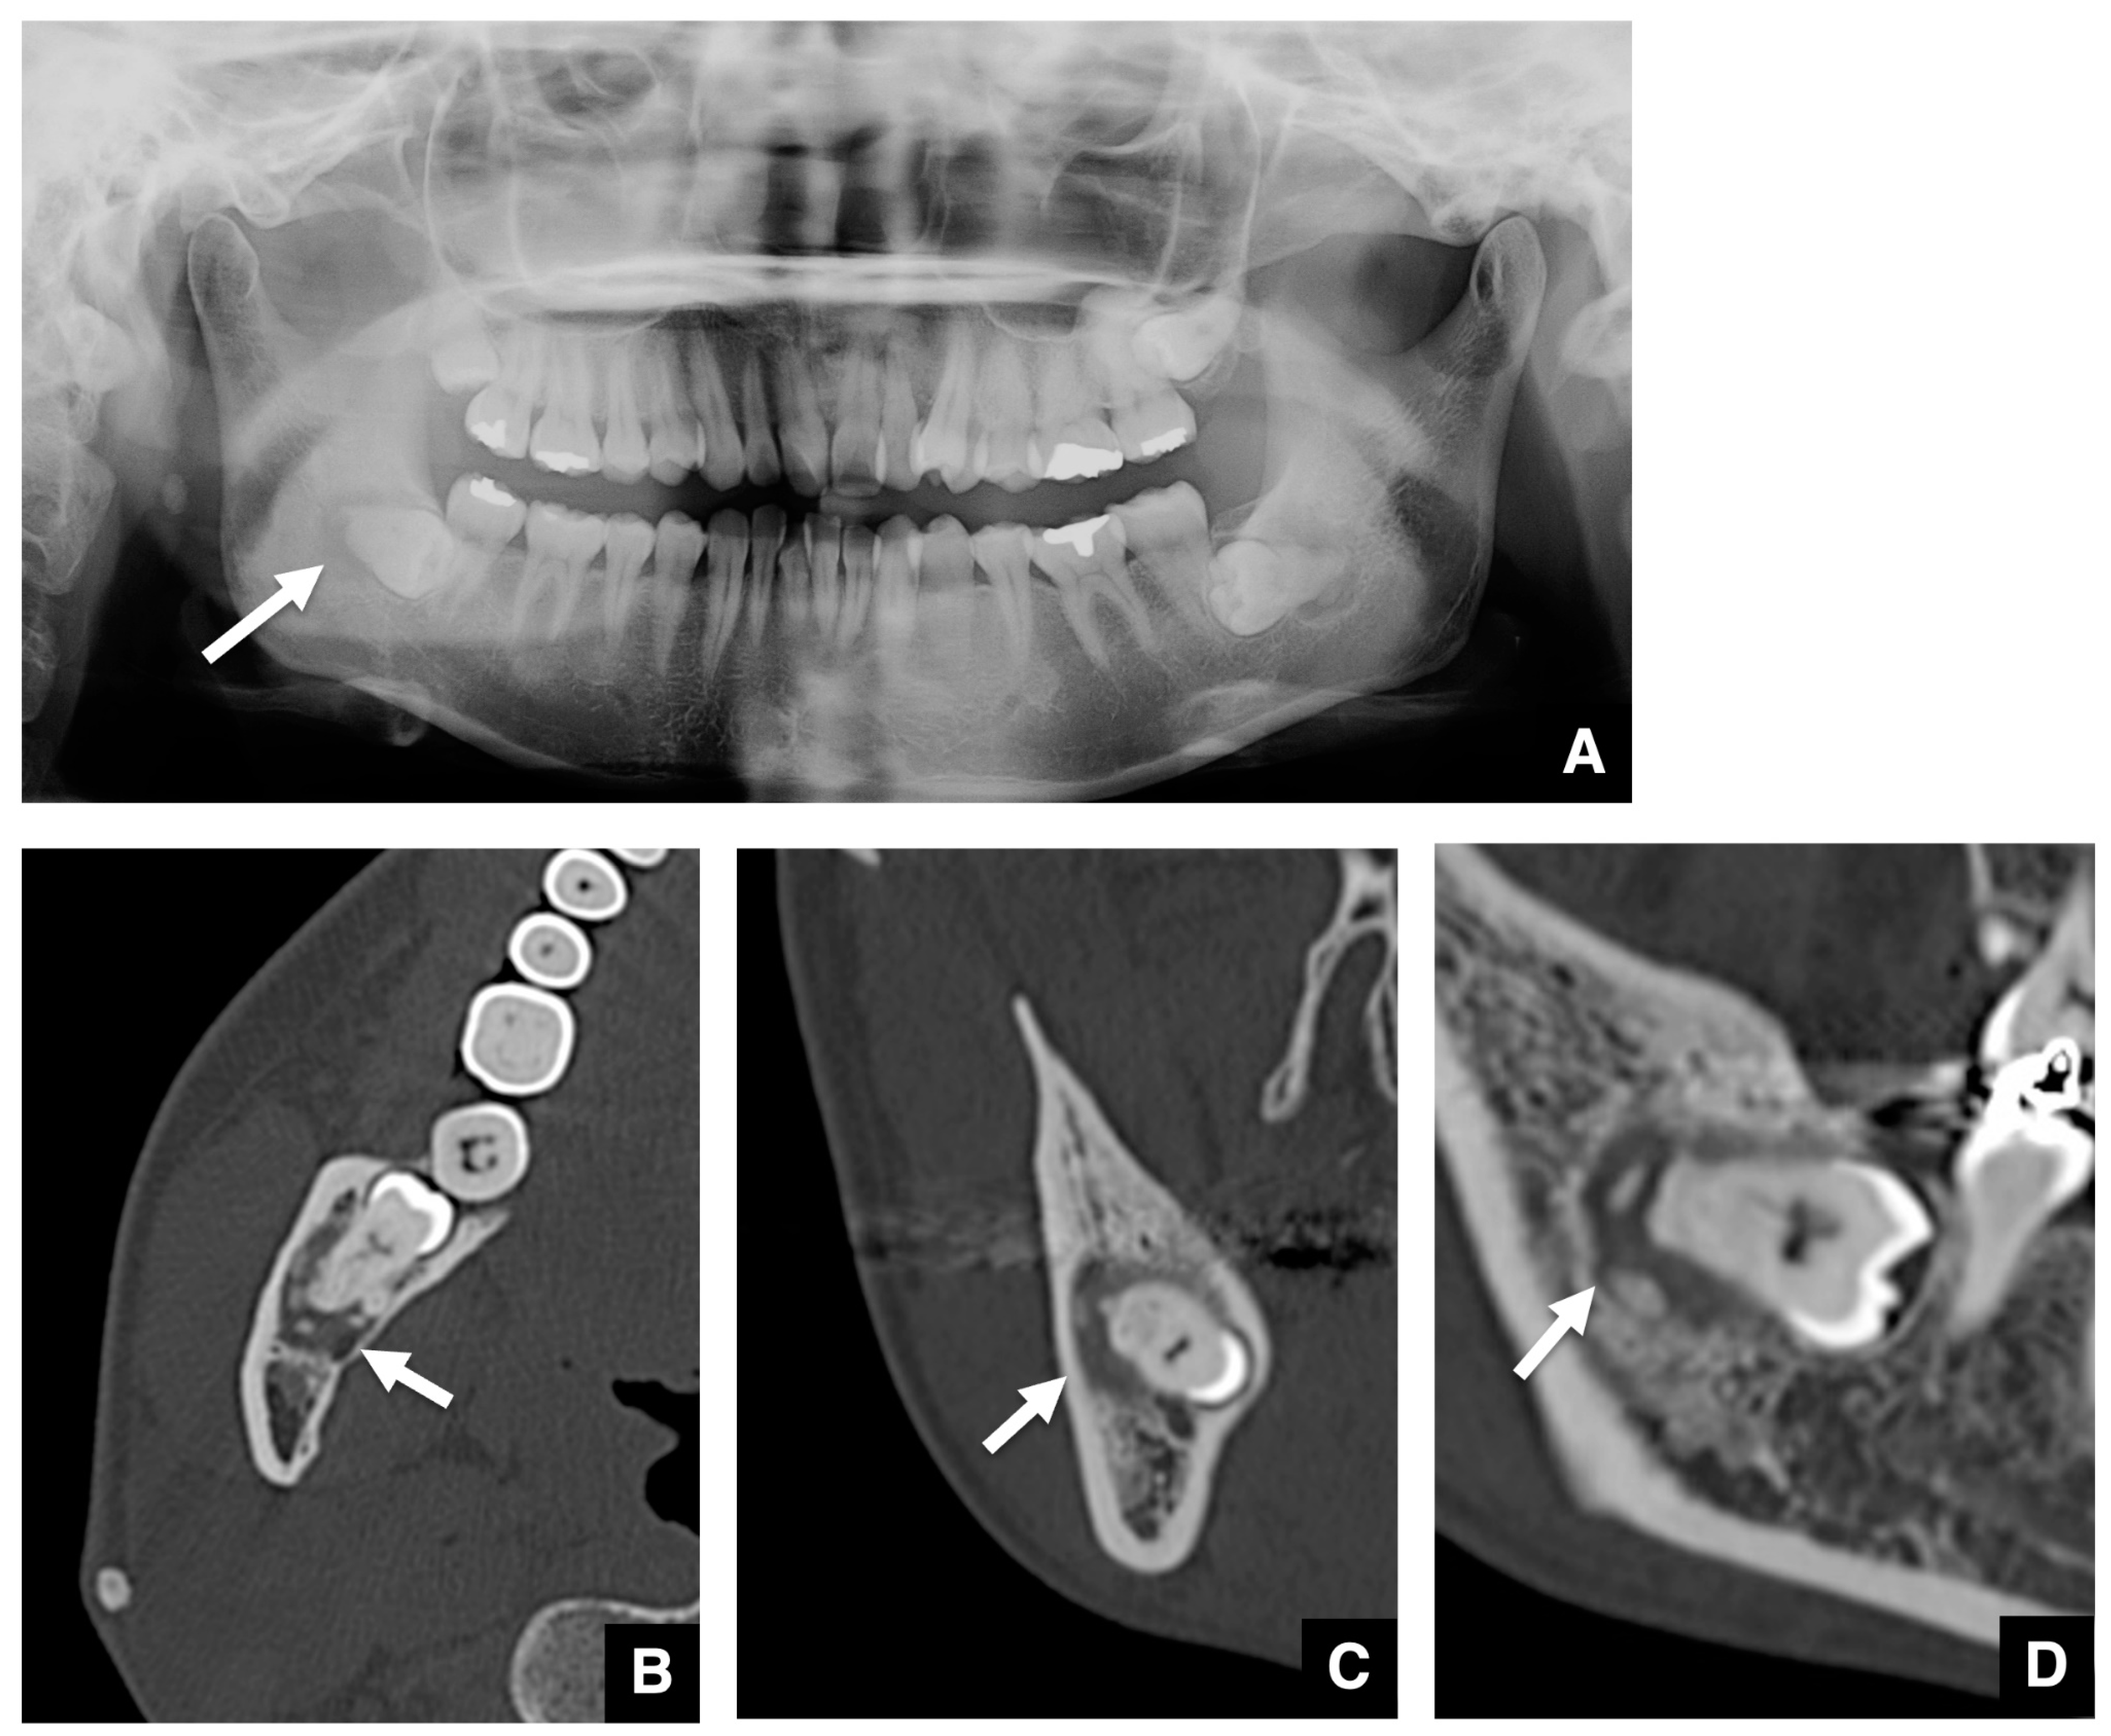

3.2. Imaging Characteristics of COD Associated with Embedded Teeth

| 48 | F | Left | Focal | Second | Round | 7.0 × 4.3 × 7.1 | Horizontal | Well-defined | Thin | Undetectable | Smooth | Present | Radiopaque dots | Distinct | Present | Present | Absent |

| 33 | F | Right | Focal | Second | Round | 8.6 × 7.0 × 7.2 | Horizontal | Well-defined | Thick | Crescent | Not smooth | Present | Uniform calcification | Distinct | Present | Absent | Absent |

| Left | Focal | Second | Round | 7.9 × 7.3 × 7.1 | Horizontal | Well-defined | Undetectable | Undetectable | Smooth | Present | Radiopaque dots | Partial contact | Present | Absent | Present | ||

| 35 | F | Right | Focal | First | Round | 9.1 × 8.6 × 10.4 | Horizontal | Ill-defined | Thin | Undetectable | Smooth | Absent | Undetectable | Distinct | Present | Absent | Present |

| 39 | F | Right | Focal | Second | Round | 14.8 × 8.5 × 9.9 | Horizontal | Well-defined | Undetectable | Crescent | Smooth | Present | Uniform calcification | Distinct | Absent | Absent | Present |

| 47 | F | Right | Focal | Second | Irregular | 8.4 × 6.0 × 9.7 | Vertical | Well-defined | Undetectable | Pearls | Not smooth | Absent | Massive calcification | Partial contact | Present | Absent | Present |

| 42 | F | Left | Focal | Second | Irregular | 10.2 × 5.6 × 13.0 | Horizontal | Well-defined | Undetectable | Multiple dots | Smooth | Present | Radiopaque dots | Distinct | Present | Absent | Present |

| 51 | F | Right | Focal | Second | Round | 9.8 × 6.2 × 5.8 | Horizontal | Ill-defined | Undetectable | Crescent | Smooth | Present | Uniform calcification | Partial contact | Absent | Absent | Present |

| 33 | F | Left | Focal | Second | Round | 10.3 × 8.7 × 11.5 | Vertical | Ill-defined | Undetectable | Multiple dots | Smooth | Present | Massive calcification | Contiguous | Present | Absent | Present |

| 62 | M | Right | Focal | First | Round | 6.0 × 2.9 × 5.7 | Horizontal | Well-defined | Undetectable | Undetectable | Smooth | Present | Undetectable | Distinct | Absent | Absent | Absent |

| 44 | M | Left | Focal | First | Round | 8.7 × 5.7 × 5.8 | Horizontal | Ill-defined | Undetectable | Undetectable | Smooth | Absent | Undetectable | Distinct | Absent | Absent | Absent |

| 45 | F | Right | Florid | Second | Round | 11.9 × 8.6 × 11.7 | Horizontal | Ill-defined | Undetectable | Undetectable | Smooth | Present | Multiple radiopaque dots | Partially contact | Absent | Absent | Present |

| Left | Florid | Second | Round | 10.2 × 5.6 × 11.9 | Horizontal | Ill-defined | Thin | Multiple dots | Not smooth | Present | Multiple radiopaque dots | Partially contact | Present | Absent | Present | ||

| 38 | F | Left | Focal | Final | Round | 13.2 × 9.8 × 10.2 | Horizontal | Well-defined | Thick | Pearls | Not smooth | Absent | Uniform calcification | Contiguous | Present | Absent | Absent |

| 35 | F | Left | Focal | Second | Round | 11.7 × 7.1 × 10.0 | Horizontal | Well-defined | Thin | Multiple dots | Smooth | Present | Radiopaque dots | Partial contact | Present | Absent | Present |